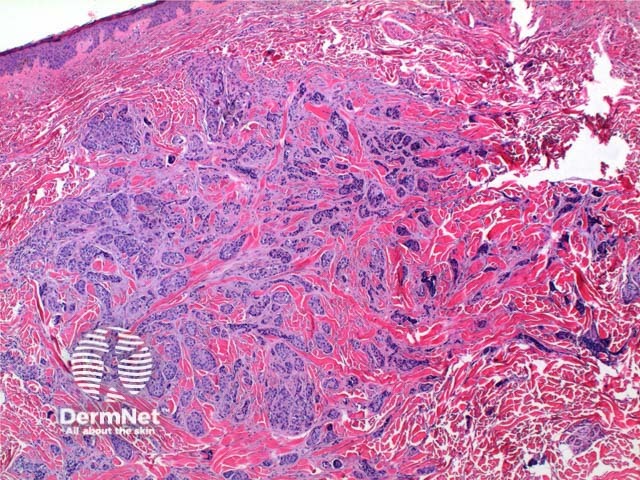

The histology of metastatic adenocarcinoma may show a number of patterns. Low power view frequently shows a poorly circumscribed infiltrating tumour centred on the dermis (Figure 1). Cords and nodules of atypical epithelial cells can be seen dissecting between collagen bundles (Figure 2). These may show evidence of duct or gland formation (Figure 3), and may be set in a mucinous stroma (Figure 4). Vascular and lymphatic permeation may be evident in the telangiectoides and erysipeloides variants of breast metastases.

Figure 1